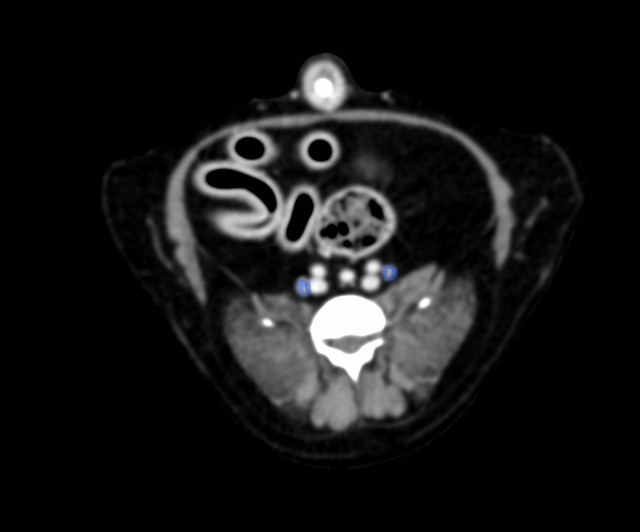

次いで手術の是非と可否を検討するためCT検査を実施した結果、附属リンパ節や肝臓、肺などへの転移は認められなかったため、一部の直腸と一部の肛門括約筋を含めて腫瘍を摘出した。